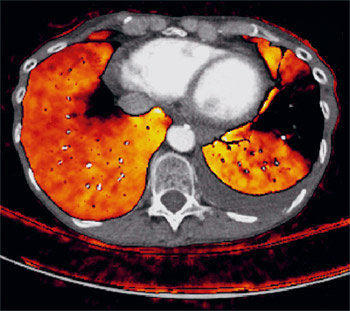

Abb.1

Lungendurchblutung: Der keilförmige dunkle Bezirk rechts entspricht dem nicht mehr durchbluteten Lungenareal aufgrund eines Blutgerinnsels (Lungenembolie in einem Lungenarterienast).